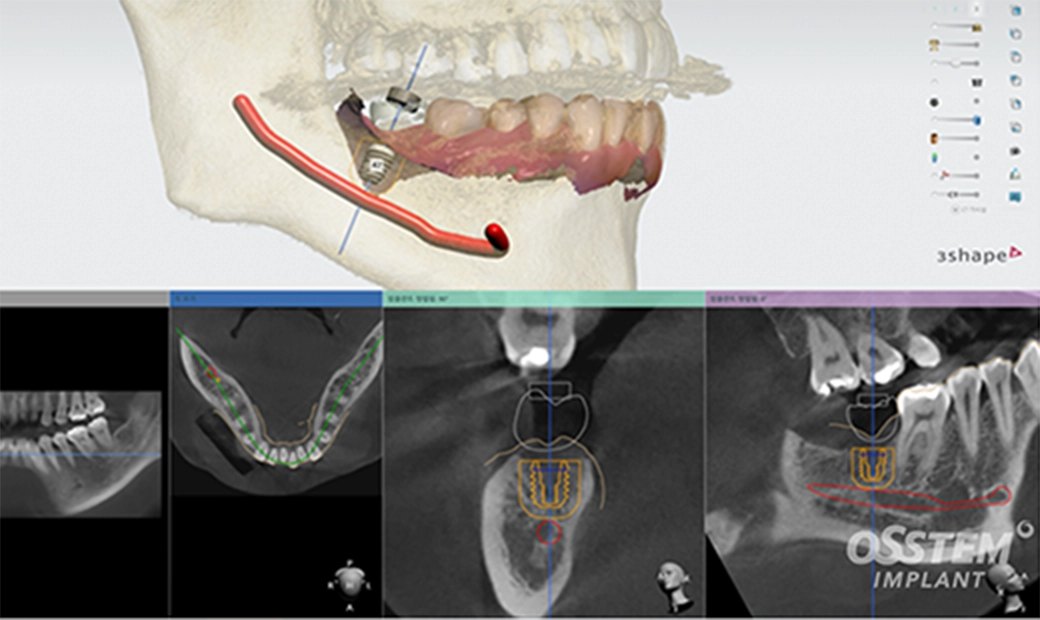

治療の流れ

-

01

検査(CT・口腔内スキャン)

歯科用CTと口腔スキャナーで口腔内を撮影し、詳細な3次元データを取得します。

歯、骨の状態や神経、血管の位置などを精密に把握します。

02

被せ物の設計

最終的に取り付ける人口歯を製作するために、お口の中を型取り、設計します。

03

3D治療計画

CTとスキャナーで取得したデータを組み合わせ、シュミレーションソフトで3D画像を確認しながら、理想のインプラント埋入位置を計画します。

04

サージカルガイド作製

治療計画を元に、患者様専用のサージカルガイドを3Dプリンターで作成します。サージカルガイドは透明なプラスチック製です。